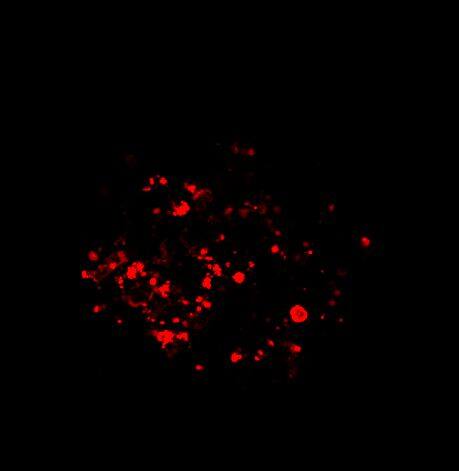

为了生成 3D 球体,将 NCI-H460 细胞(源自非小细胞肺癌)以两种不同的密度接种在超低吸附培养板中:3×103 个细胞/孔或 700 个细胞/孔。在直径分别达到约 400-500 或 150-200 um 后,用细胞毒素剂处理球体 6 天。通过使用钙黄绿素 AM 和碘化丙啶 (PI) 的活/死染色来观察和评估药物的效果。钙黄绿素 AM 是一种细胞渗透性染料,用于测定细胞活性。非荧光钙黄绿素 AM 在活细胞中被细胞内酯酶水解后转化为(绿色)荧光钙黄绿素。PI 是一种红色荧光核染色剂,通常用于检测死亡细胞,因为它不能进入完整的活细胞。最后,使用 Hoechst 染料将细胞核染成蓝色。

我们采用 CrestOptics X-Light V3 转盘共聚焦结合 Prime BSI 相机(Photometrics,像素尺寸 6.5 um)进行采集。我们比较了使用 20 倍空气物镜(CFI Plan Apo Lambda,尼康,0.7 NA 和 1mm WD)和 25 倍硅油物镜(CFI Plan Apo Lambda S,尼康,1.05 NA 和 0.55 mm WD)进行的采集。在图 A 中,我们展示了从总共 150 um 的 Z 堆栈中获得的最大强度投影 (MIP) 图像;特别是,使用 20 倍空气物镜和 25 倍硅油物镜获得了相同的球体。图 B 显示了使用两种物镜获得的 3D 球体同一区域的放大。

图 A:使用 20 倍空气物镜(顶部)和 25 倍硅油物镜(底部)获得的肿瘤球体 Z 堆栈的最大密度投影 (MIP)。活细胞用钙黄绿素(绿色)标记,死细胞用 PI(红色)标记。细胞核用 Hoechst(蓝色)染色。比例尺:100 um。这些图像是使用 CrestOptics X-Light V3 转盘获取的。

图 B:使用 20 倍空气物镜(左)和 25 倍硅胶物镜(右)获得的 3D 球体同一区域的放大。活细胞用钙黄绿素(绿色)标记,死细胞用 PI(红色)标记。细胞核用 Hoechst(蓝色)染色。这些图像是使用 CrestOptics X-Light V3 转盘获取的。